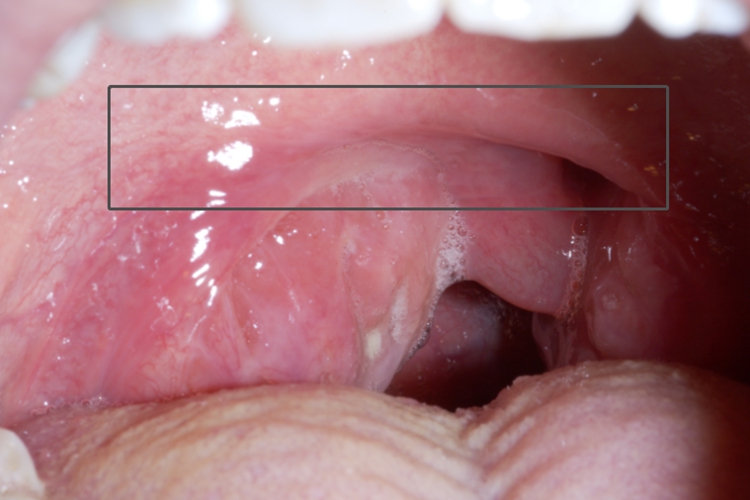

表现为面颊赤红、畏寒发热,全身疲乏无力,患侧腭舌弓及软腭高度红肿,悬雍垂肿胀偏向健侧,腭舌弓上方隆起,扁桃体常被遮盖且被推向内下方。颈部活动受限,头常偏向患侧,颌下淋巴结肿大、压痛。

表现为软腭充血发红、水肿,出现针尖大小的红点,局部有灼热不适感,很快发展成溃疡,溃疡表浅,直径为5-10mm,表面微凹,被覆一层淡黄色假膜,周围有明显的红晕,有较剧烈的烧灼痛。

可在软腭出现群集性小水疱,很快破溃形成表浅溃疡,也可开始即表现为红斑、浅溃疡。疼痛较明显,可伴有发热、咽痛及局部淋巴结肿痛。自然病程1-2周。